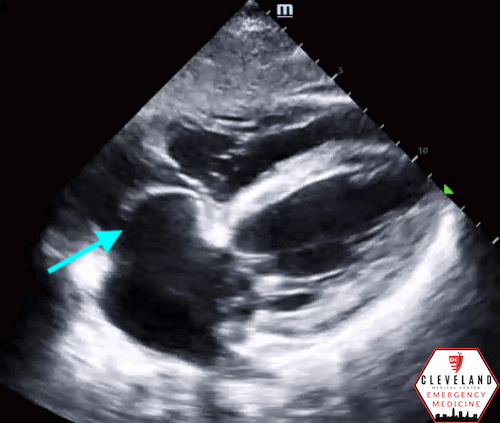

LV function is preserved, there’s no pericardial effusion or signs of right heart strain. There is, however, a large left atrial aneurysm, best seen in the apical 4 chamber view and especially in the subxiphoid view. When color doppler was applied, there was no significant mitral (or other valvular) regurgitation or abnormalities. No prior images to compare.